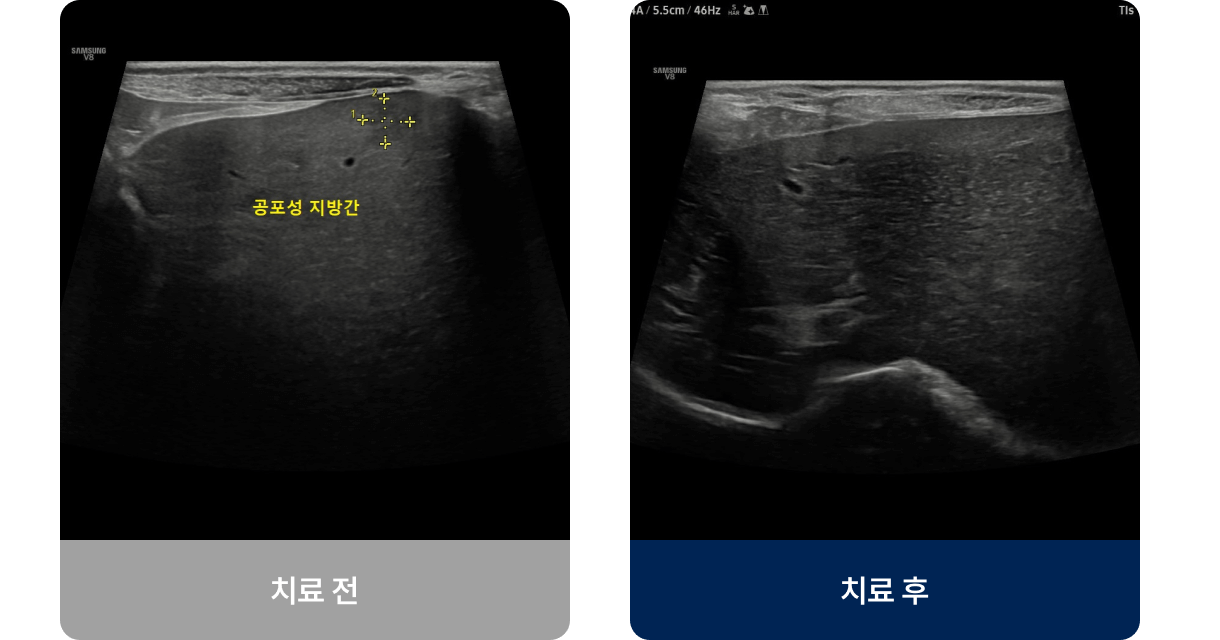

영양 불균형, 약물, 독성물질, 염증, 종양 등의 원인으로 간의 해독과 대사 기능이 저하되는 질환입니다. 주로 중·노령견이나 고양이에게 많이 발생하며 식욕 부진, 구토, 황달(눈·잇몸이 노래짐) 등의 증상이 나타납니다. 진행되면 체중 감소, 복부 팽창, 무기력 등 전신적인 증상으로 악화될 수 있습니다.